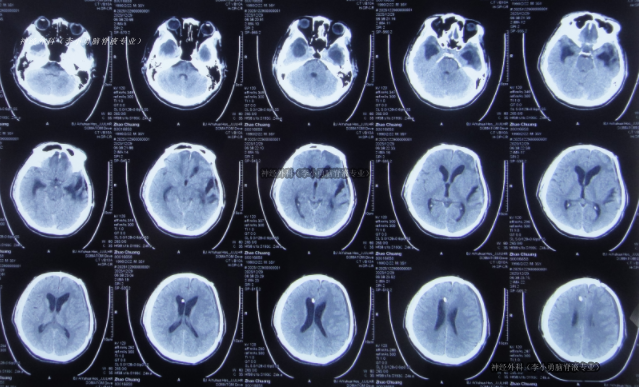

入院時:意識模糊,右上肢活動差,鼻飼、留置尿管。CT示顱骨缺損、腦積水、腦膨出。